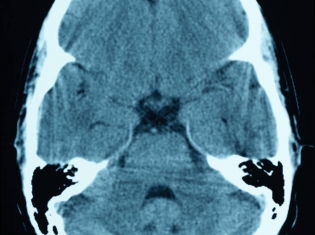

Research leader Philip LoGrasso said the study provides the first compelling data on an oral, brain-penetrating inhibitor to demonstrate this effectiveness in Parkinson's disease, a progressive, neurodegenerative disease that causes tremor and coordination problems from the loss of a group of neurons in part of the midbrain involved in motor control.

The compound -- a molecule known as SR-3306 -- impairs a class of enzymes called c-jun-N-terminal kinases (JNK, pronounced "junk"). JNK enzymes play a vital role in the survival of neurons (nerve cells) and have become a target for drugs to treat Parkinson's.